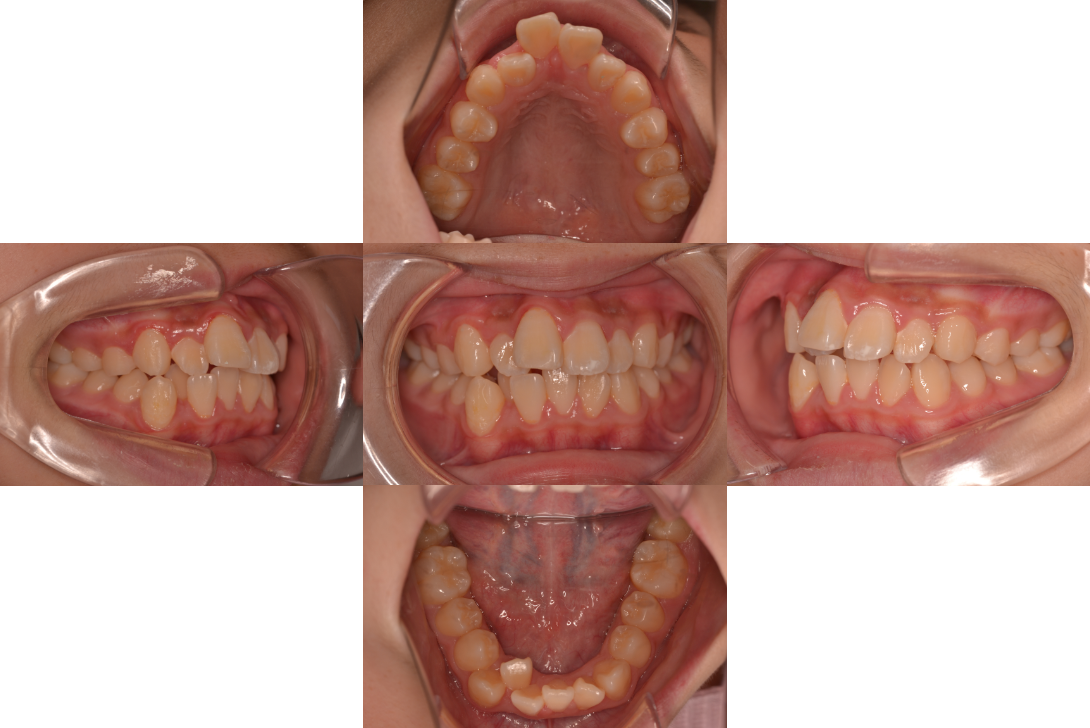

叢生をフルDBSで改善した症例

※DBSとはダイレクトボンディングシステムと呼ばれており、ブラケットにワイヤーを通して歯を動かしていく矯正治療です。

患者情報

18歳女性

主訴

歯並びがガタガタ

行った治療内容

フルDBS

治療のリスク

歯肉退縮、歯根吸収

治療期間

動的治療期間2年4か月

※ クリックして拡大することができます。